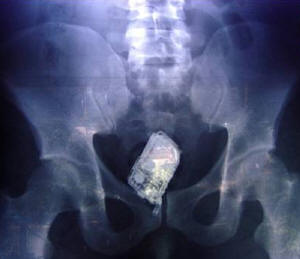

El Salvadorban a napokban lefüleltek négy elítéltet, akik illegális módon mobiltelefonnal rendelkeztek a büntetőintézetben. A Zacatecoluca-ban található börtönben az őrök akkor lettek figyelmesek az engedély nélkül tartott készülékekre, amikor röntgenfelvételeket készítettek a rabokról.

Jaime Villanova, az intézet szóvivője elmondta, hogy a Mara Salvatrucha nevezetű alvilági banda négy tagja műanyag zacskóba tette mobilját, majd pedig a végbelébe rejtette azt. A röntgen vizsgálat során egyébként nem csak telefonokat, hanem mobil töltőket is találtak az őrök.